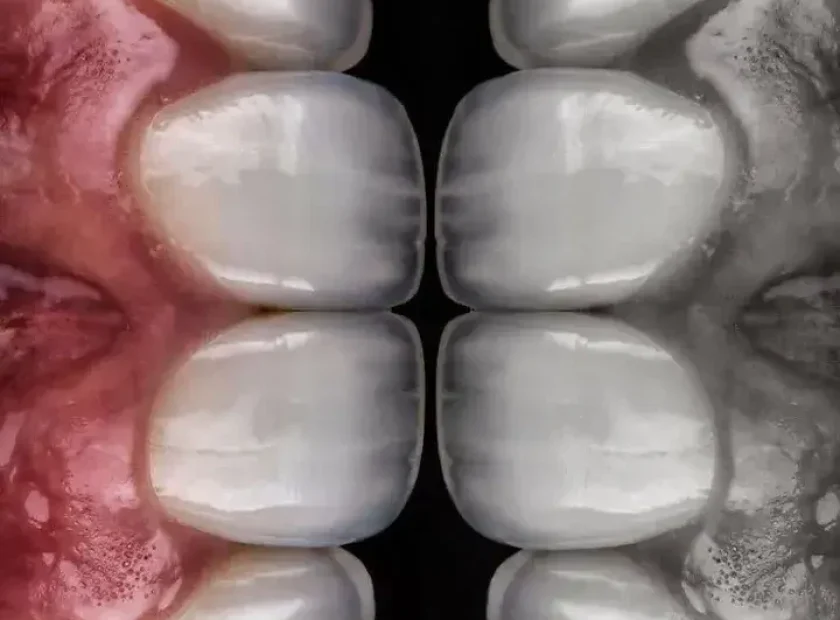

جرمگیری دندان جلو با پلاک دندانی شدید و خونریزی لثه

التهاب لثه و خونریزی بعد از جرمگیری دندان در دندانهای جلویی

جرم دندانی ضخیم و التهاب قرمز لثه